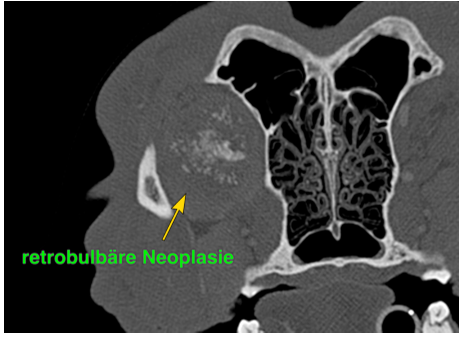

Bei Rottweiler Rocky war die Nickhaut bereits seit Wochen etwas vorgefallen und im Ultraschall erhärtet sich der Verdacht auf einen Tumor. Im CT konnte dann eine riesige Masse dargestellt werden und auch ein vergrößerter Lymphknoten. Die Biopsie ergab einen Tumor unklarer Herkunft, sodass wie zuerst keine sichere Prognose stellen konnten. Aber es sah nicht gut aus.